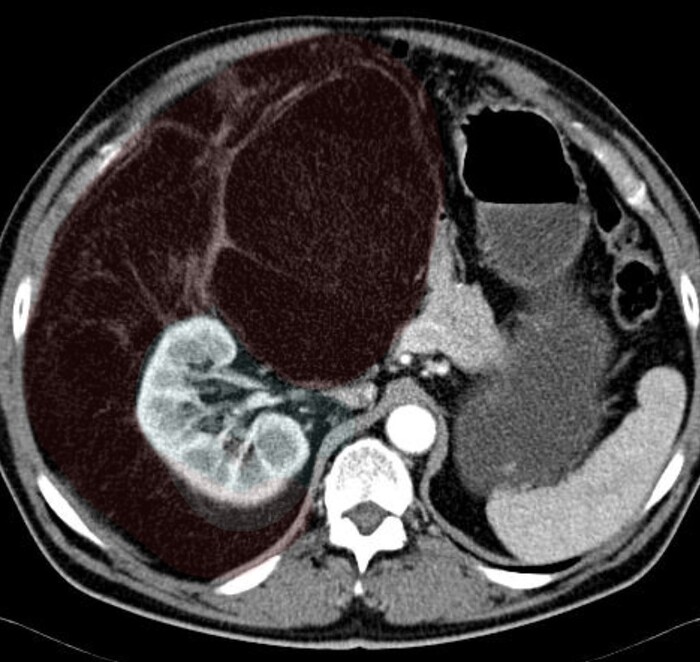

Было проведено КТ-обследование органов брюшной полости, где обращало на себя внимание необъятное объёмное жиросодержащее образование в забрюшинном пространстве с эпицентром справа, заполняющее собо практически весь живот:

Образование (красным) охватывало со всех сторон правую почку (голубым):

И имело солидный компонент:

Признаков инвазии (прорастания) в окружающие органы не было.

Согласно радиологической картине был выставлен предварительный диагноз забрюшинной липосаркомы.

Гистологический диагноз: высокодифференцированная забрюшинная липосаркома.